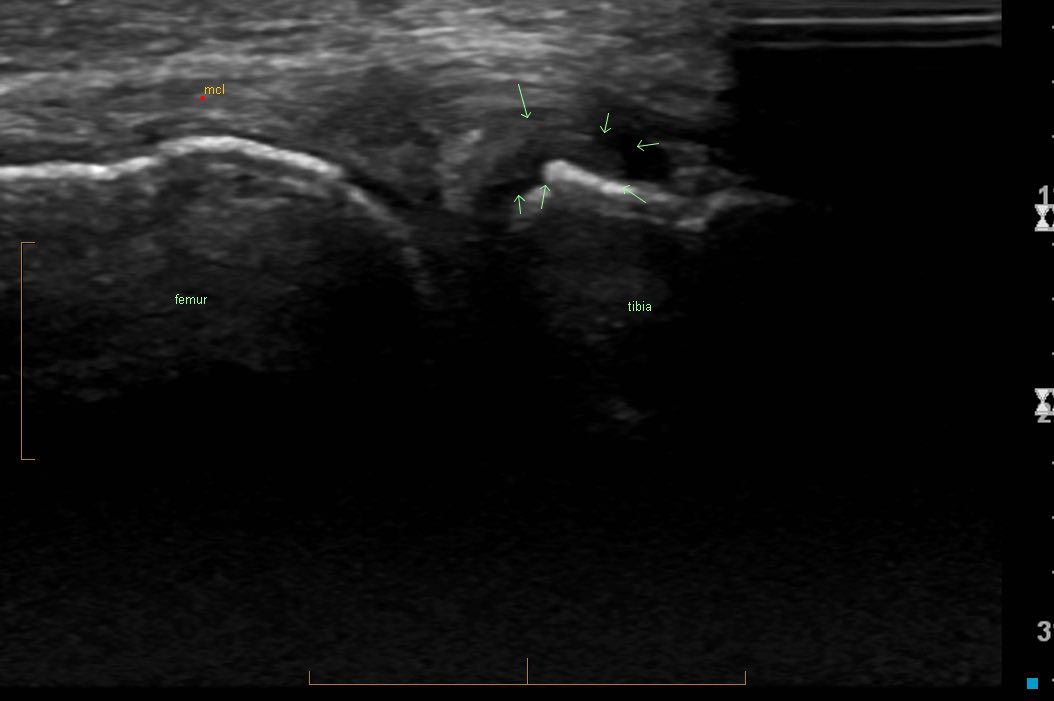

6. Deep MCL insufficiency

Oft overlooked cause of chronic medial knee Sx after MCL trauma

Deep fibres check rotational forces

Pain or 'instability' on forceful side foot kick, getting 'around the ball', twisting

⬆️ rotation on anteromedial drawer test, ? valgus laxity